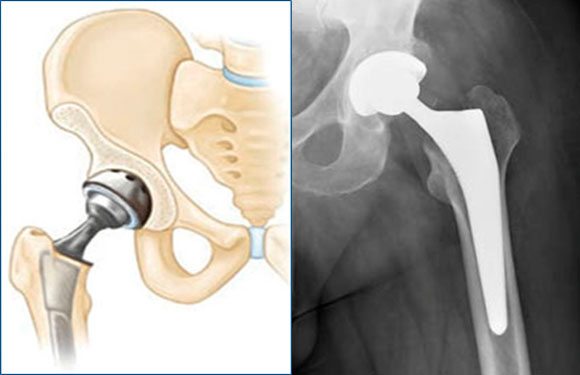

Эндопротезирование суставов — операционное вмешательство для замены поврежденного сочленения имплантатом. Когда суставы претерпевают сильные дегенеративно-дистрофические процессы, их полная или частичная замена – единственный шанс для пациентов вернуться к нормальной жизни.